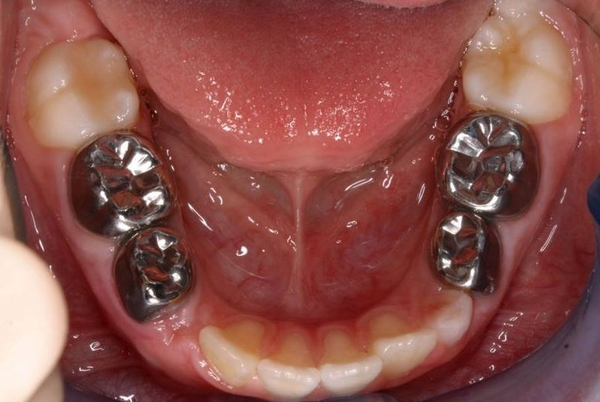

Chụp thép răng sữa là phương pháp sử dụng mão kim loại làm từ thép không gỉ chuyên dụng trong nha khoa để bao phủ toàn bộ thân răng sữa đã bị tổn thương nặng. Mão thép này được thiết kế phù hợp với kích thước răng trẻ em và được gắn cố định bằng xi măng nha khoa chuyên dụng.

Khác với trám răng chỉ phục hồi một phần mô răng bị mất, chụp thép răng sữa bao bọc toàn bộ thân răng, giúp bảo vệ tối đa cấu trúc còn lại, ngăn vi khuẩn xâm nhập và kéo dài tuổi thọ của răng sữa cho đến khi răng vĩnh viễn mọc thay thế.

Tính thẩm mỹ không cao là yếu tố khiến nhiều phụ huynh băn khoăn. Mão thép có màu kim loại, dễ nhận thấy khi trẻ cười nếu chụp ở răng phía trước. Tuy nhiên, trên thực tế, chụp thép răng sữa thường được áp dụng nhiều cho răng hàm phía trong nên ít ảnh hưởng đến thẩm mỹ.

Ngoài ra, trong một số ít trường hợp, mão có thể bị bong nếu trẻ ăn nhai thực phẩm quá cứng hoặc chăm sóc không đúng cách. Tuy nhiên, tỷ lệ này tương đối thấp nếu được gắn đúng kỹ thuật.